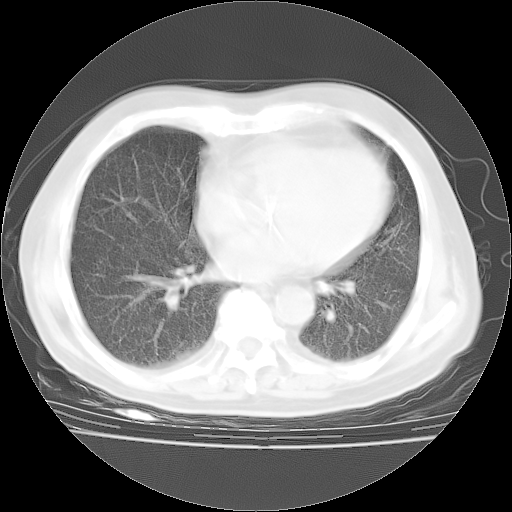

4月28日肺部CT——再次出现类似去年5月9日——透光度降低,“间质性”改变。

4月28日肺部CT——再次出现类似去年5月9日——磨玻璃样、间有“粟粒样”改变。